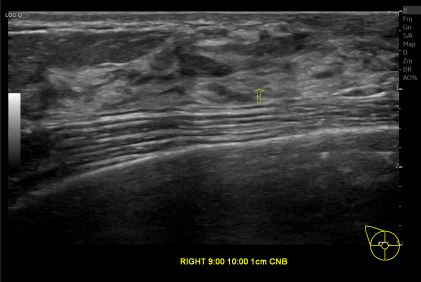

상기환자는 유방 추적관찰 위해 내원하신 50대 중반 여성분으로 의심스러운 우측 혹 조직검사 시행해 제자리암 진단되었습니다.